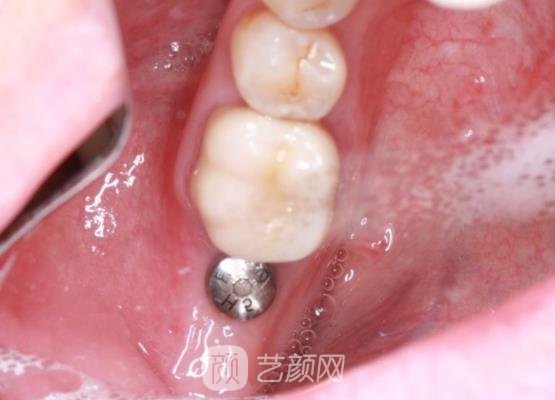

种植牙案例:

今天我到医院进行牙冠安装的时候,医生的态度和手法还是一如既往的温和,所以手术全程给我的感觉是很不错的,自从自己的牙齿恢复到正常之后,感觉整个人在外观和自信方面都有了很大的提升,这使我感到好开心,以后会近期到医院进行种植体维护的,希望我的种植牙能够维持的更久更稳定吧。